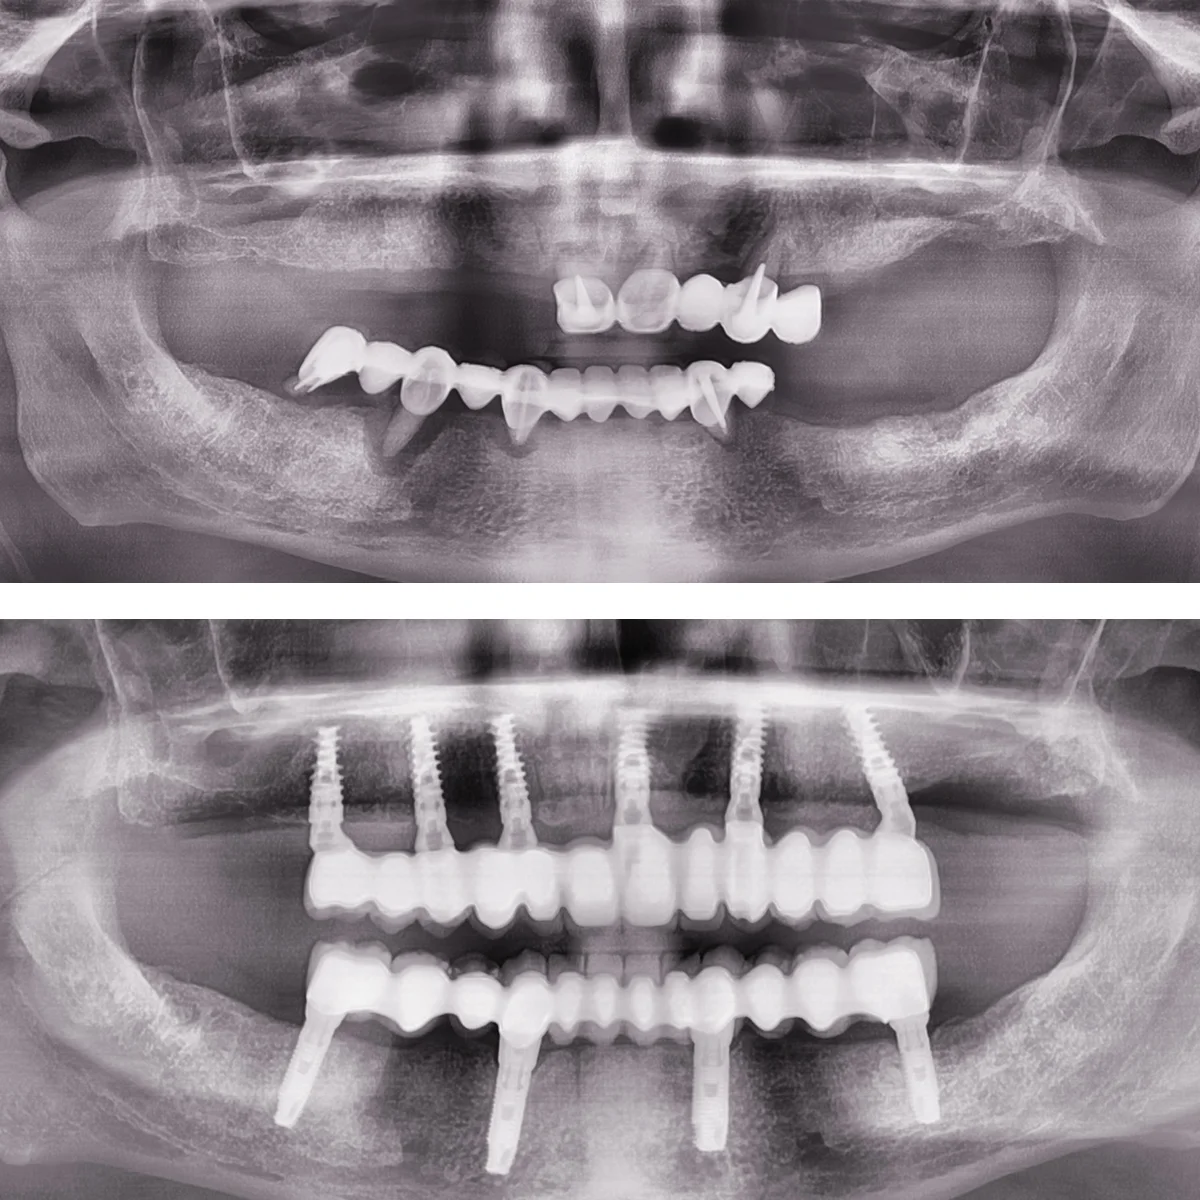

Dinți Ficși în 8-24 de ore pe implanturi dentare cu tehnica All-on-4/All-on-6 este cea mai eficientă și rapidă metodă de restaurare totală a danturii.

- Aplicare lucrare provizorie pe implanturi

- Lucrarea finală